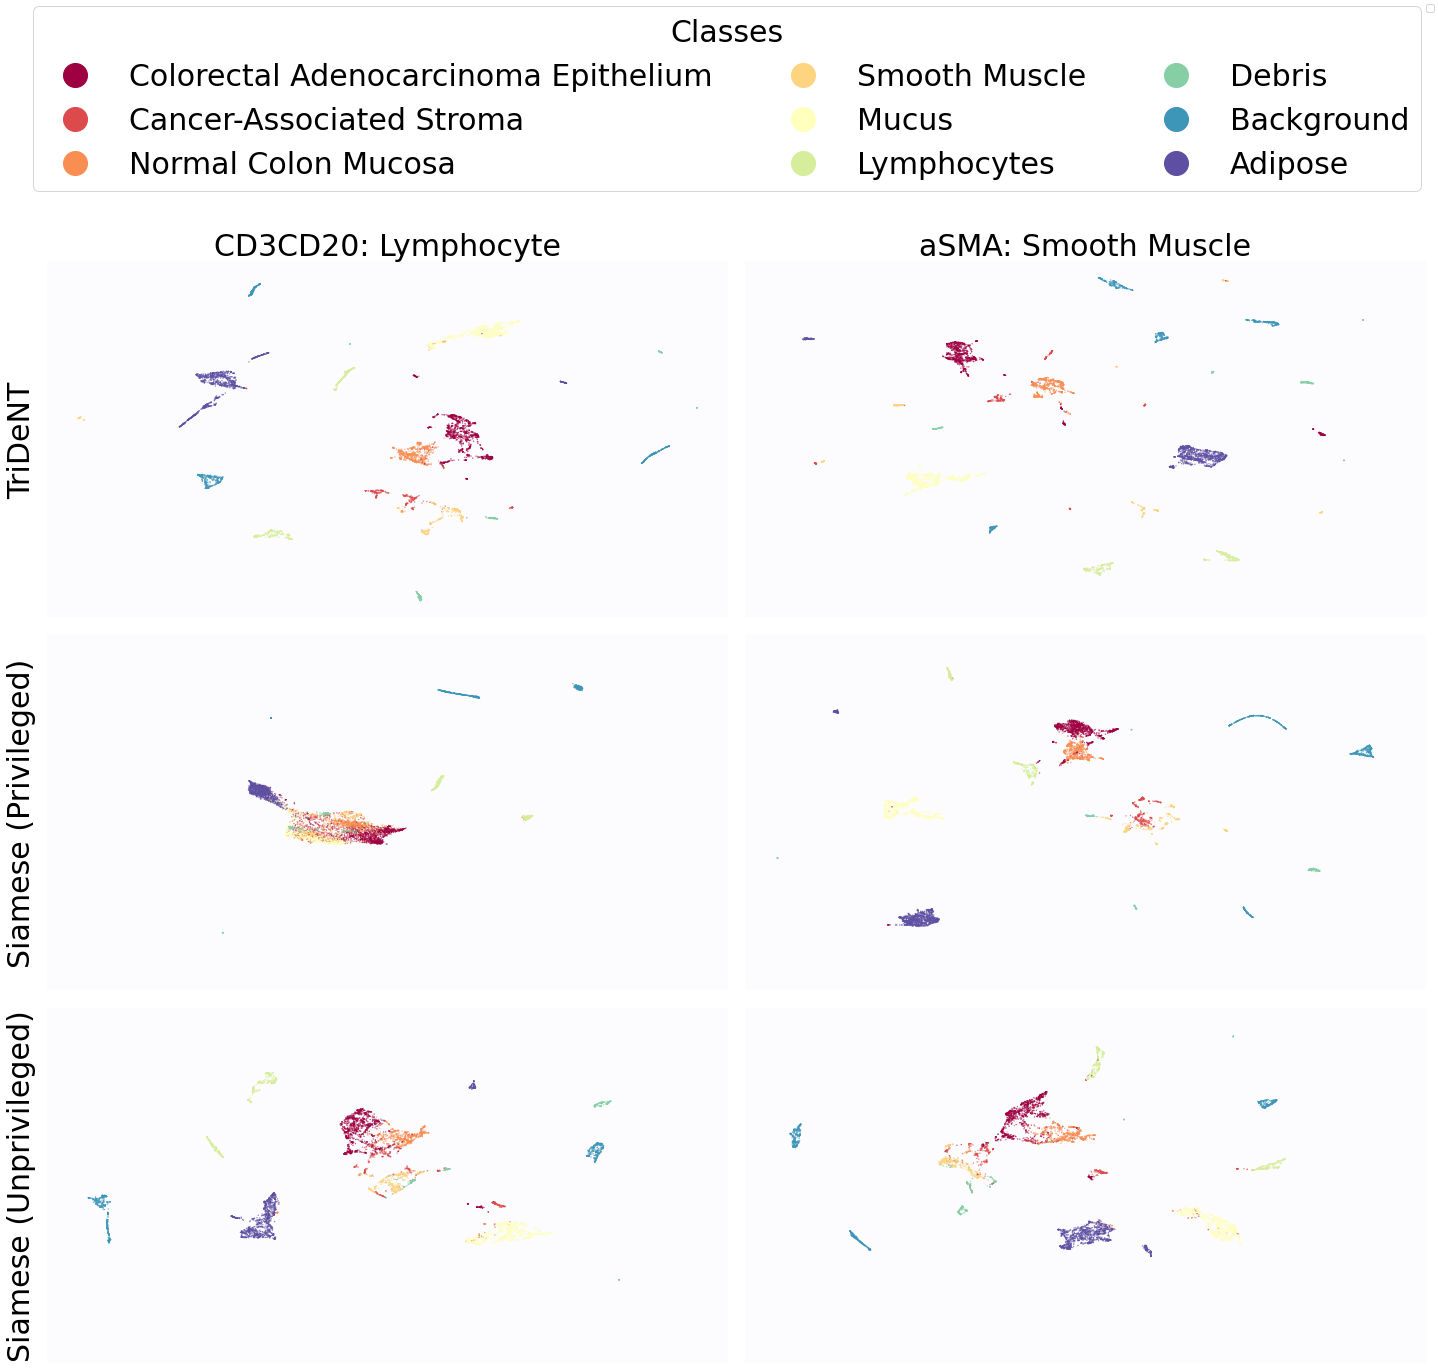

2.5 TriDeNT ♆ Identifies Features of Both Primary and Privileged Inputs from Primary Input Alone

To further analyse the learned representations, we produce UMAP projections of the latent space labelled with the tissue types for the NCT tissue type classification task, as shown for CD3CD20 and SMA in Figure 4(a), and for all SegPath stains in Figures S8 and S9. These figures make the reasons for the varying performance of the privileged Siamese model more apparent. For stains with better performing privileged Siamese models, such as SMA, the UMAPs are very similar between Siamese methods and TriDeNT, with well-differentiated tissue type clusters. In those with worse performance, such as ERG, the tissue types are poorly differentiated, often with only adipose and background forming distinct clusters from the other classes. On closer inspection, it is notable in these projections that TriDeNT ♆ produces more well-defined and separated clusters in general than Siamese networks. This is further evidenced in Figure S7, where TriDeNT ♆ is shown to identify clusters with overexpression of a given gene significantly more effectively than an unprivileged Siamese model.